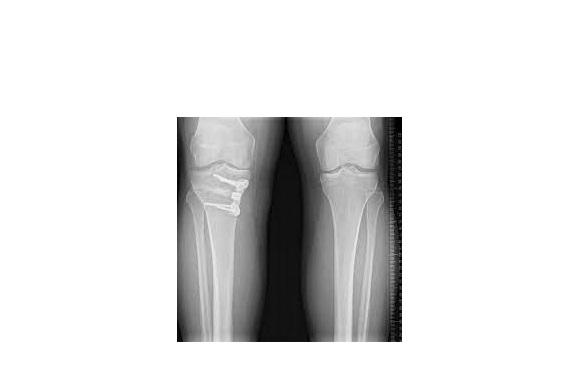

High tibial osteotomy (HTO) is a surgical procedur...

View Details